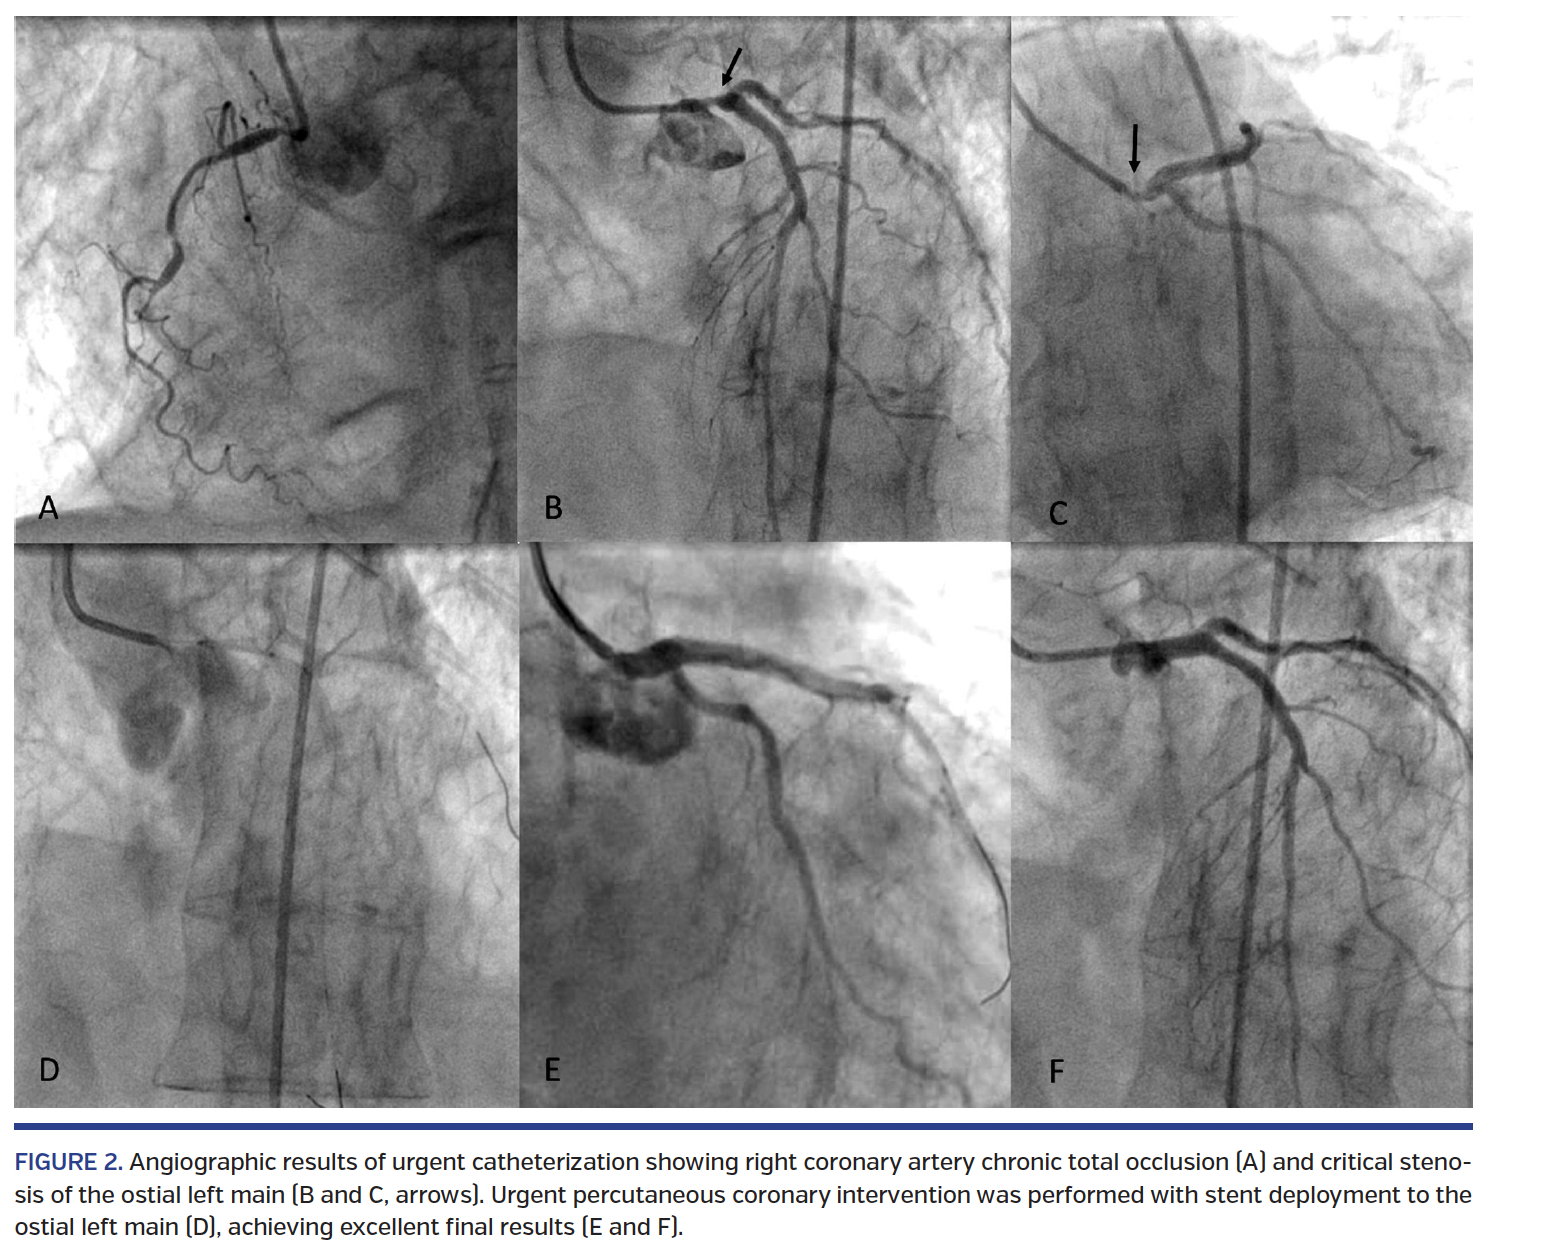

Coronary angiography was performed via left femoral access (which was the only palpable arterial access) and revealed a critical ostial left main (LM) stenosis, apart from the known RCA-CTO (Figure 2). The case was immediately discussed with the cardiac surgeons, but cardiac surgery in the context of hemodynamic instability and ongoing ischemia was considered a prohibitive risk. Thus, emergency PCI was selected as the first treatment in order to try and stabilize hemodynamics by relieving myocardial ischemia. Due to right femoral pulse weakness (in the setting of known peripheral arterial disease), we decided to perform emergency LM-PCI with no intraaortic balloon pump support. An extra-backup 3.5 guide catheter was selected to quickly cannulate the LM, and lesion predilation with a 4.0 non-compliant balloon was then performed. A zotarolimus-eluting stent was implanted into the LM. Angiographic final result was excellent (Figure 2), ST-segment depression resolved, and hemodynamics started to improve, so the patient was transferred to our critical care unit. During the following 24 hours (day 1), she had a stable systolic blood pressure of 110 mm Hg (under noradrenalin infusion) and extubation was successfully performed. On day 2, in the absence of any signs of recurrent ischemia, a significant drop of BP and a global worsening of pulmonary edema (pulmonary artery pressure monitoring by Swan-Ganz catheter, 68 mm Hg) were noticed, so the decision was made for urgent BAV and a bail-out insertion of percutaneous ventricular assistance device. The patient was brought back to the catheterization laboratory, and her 6 Fr sheath in the left femoral artery was exchanged with a 10 Fr sheath to perform BAV. Right femoral venous access was obtained and a 6 Fr sheath was inserted to accommodate a temporary pacemaker. A 6 Fr Amplatz left 1 diagnostic catheter and a straight wire were used to access the LV. Under high-rate temporary pacing, BAV was successfully performed with a 20 cm balloon and peak-to-peak ventricular-aortic pressure gradient was reduced from 50 mm Hg to 25 mm Hg. Unfortunately, a significant aortic regurgitation developed as a result, with equalization of LV end-diastolic pressure and aortic diastolic pressure and 3+/4+ regurgitation at aortography. Systolic BP immediately started decreasing. Thus, we promptly proceeded to Impella CP assist device insertion. The 10 Fr sheath was exchanged with the Impella 14 Fr sheath. The Impella pump was then advanced over the dedicated 0.014˝ guidewire into the LV (Figure 3). The pump output was set at its maximal speed. The sheathless Impella catheter was fixed in position. An immediate improvement of hemodynamic parameters was observed (systolic blood pressure increased from 75 mm Hg to 105 mm Hg, pulmonary artery systolic blood pressure decreased from 68 mm Hg to 45 mm Hg) and the patient was moved back to the critical care unit, where she was kept under strict observation to unmask any possible sign of critical limb ischemia. After collegial discussion, a TAVI procedure was planned as a definitive way to treat her aortic disease (residual gradient, relevant post-BAV regurgitation). The morning after (day 3), transfemoral TAVI was performed. Left radial access was obtained as the ancillary approach to guide the procedure.3 Indeed, through left radial approach, a 6 Fr, 125 cm MP catheter was used to perform iliofemoral angiography, which showed a diffuse disease of both axes with tight calcific stenosis of the right external iliac artery and a moderate-to-severe stenosis of the left external iliac artery, which was chosen as the best axis to perform the intervention. To allow safe Impella CP removal and TAVI performance through the same (left) iliac artery axis, transradial peripheral angioplasty was performed (Figure 4). A V18 ControlWire (Boston Scientific) was positioned into the left superficial femoral artery, and 5.5 x 20 mm and 7 x 30 mm Falcon Grande balloons (Medtronic) were inflated into the left external iliac artery (Figure 4) with the Impella catheter still in place. The Impella CP catheter was then pulled back until the pump outflow hub was visible outside the skin in order to perform the “pump-rewiring” technique. To do this, a 0.014˝ Choice Extra Support guidewire (Boston Scientific) – the “access maintenance” wire – was inserted through the pump lumen to reach the inflow hub, which was inside the artery (Figure 4). Once the wire was successfully advanced into the iliac axis, low-pressure percutaneous transluminal angioplasty balloon inflation and manual compression were used to avoid bleeding from the entry site during the following steps needed to exchange the Impella with the TAVI sheath. Indeed, a 5 Fr right catheter was advanced over the coronary guidewire, which was then exchanged for a high-support 0.035˝ wire to allow 18 Fr sheath placement. Then, a 26 mm CoreValve (Medtronic) was successfully implanted (Figure 5).